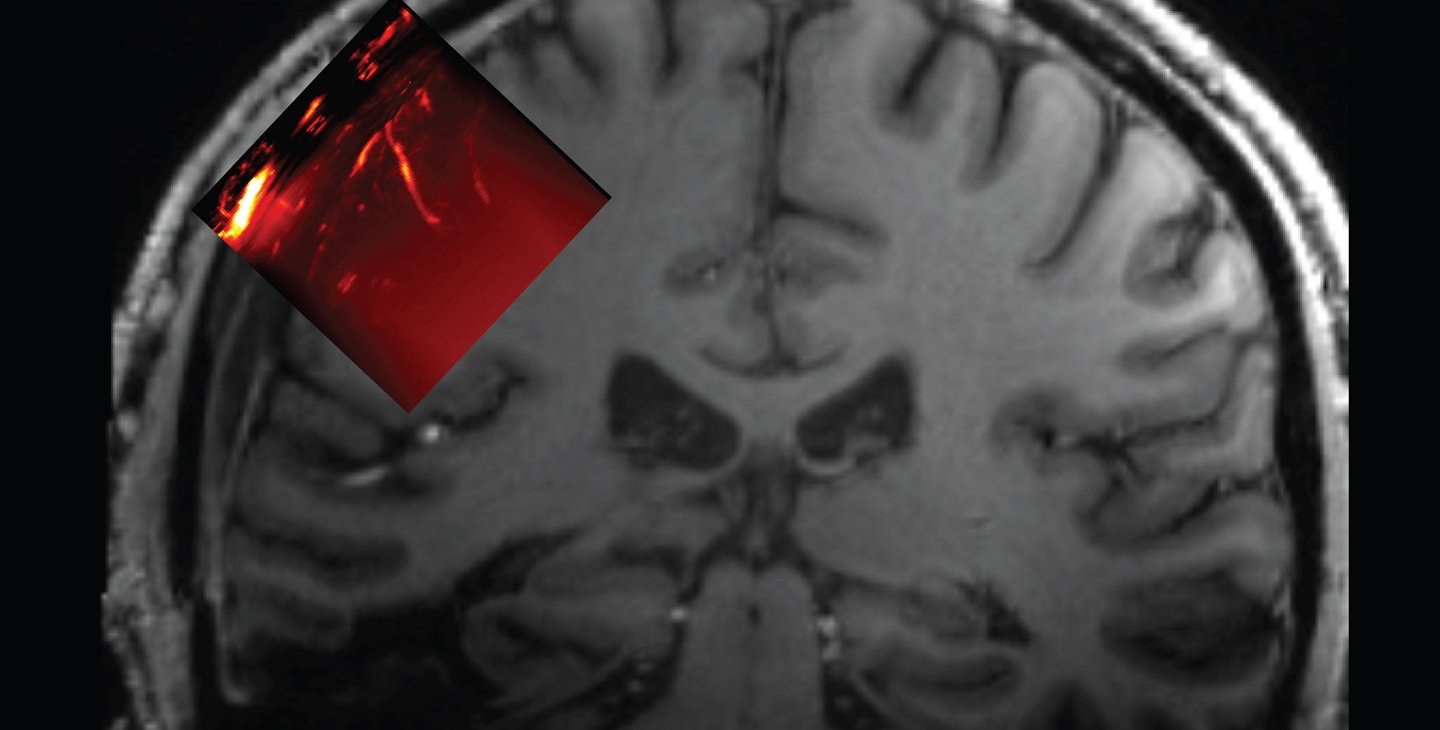

Diagnostic ultrasound works a bit like the echolocation used by dolphins or bats. High-frequency sounds are emitted and bounce off boundaries between the materials they encounter, including soft tissue and blood. Taken a step further, a technique called functional ultrasound imaging uses high frame rate imaging and computer algorithms to image blood-volume changes in the brain. When the brain's neurons are active, they use metabolic resources that are supplied via the blood stream. By measuring changes in blood volume, the researchers can infer when and where the brain's activity is changing.

The resulting implant was 4 millimeters thick overall but had a 2 millimeter-thick window through which an ultrasound transducer could image a brain region known as the posterior parietal cortex and, behind it, the motor cortex. "This area of the brain, which is important for forming intentions and carrying out motor actions, has already been thoroughly studied via other methods in our lab," Andersen says. "With ultrasound, we can image the brain up to a resolution of one-fifth of a millimeter."